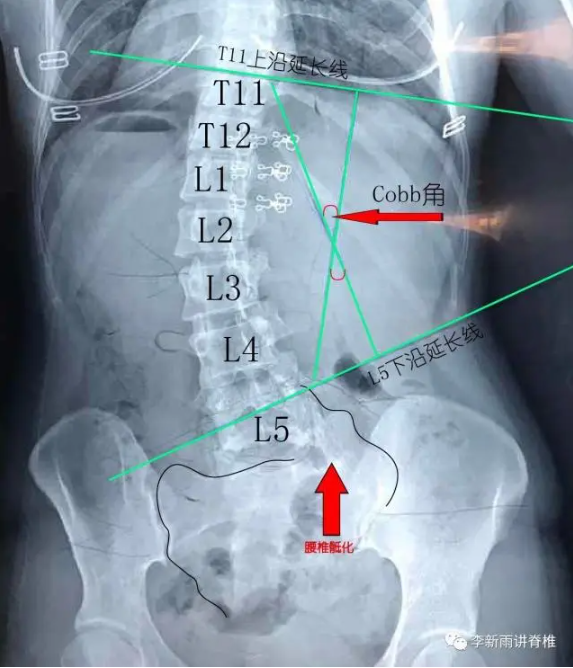

2.脊柱侧弯(Scoliosis):指脊柱在冠状面上一个或多个节段椎体偏离身体中线向侧方形成弯曲,多伴有椎体的旋转和矢状面上后凸或前凸增加或减少、肋骨和骨盆的旋转倾斜畸形以及椎旁的韧带肌肉异常,是一种脊柱的三维结构畸形。它以外观异常为主要早期临床表现,随着畸形的进展,身体躯干失平衡、背部疼痛等临床症状逐渐产生。国际脊柱侧凸研究学会对其量化,采用Cobb法评估标准站立拍摄的全脊柱正位“X”光片,通常将Cobb角≥10°定义为脊柱侧弯。其中以特发性脊柱侧弯最为常见,好发于10~16岁的青少年,以女性多见,青春期生长高峰期容易进展。

5. Cobb角:评估脊柱侧弯严重程度的重要指标,一般角度越大代表着侧弯越严重,其测量是在全脊柱正位“X”光片上,通过选择弯曲两端最倾斜的椎体(即上、下端椎体),沿其上下终板做平行线,这两条线所形成的夹角称为Cobb角。